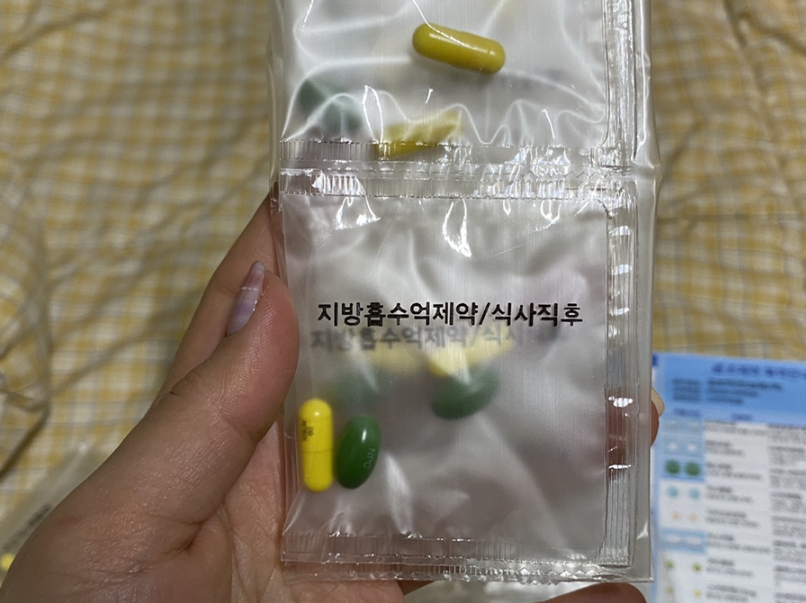

체질별 다이어트 처방약